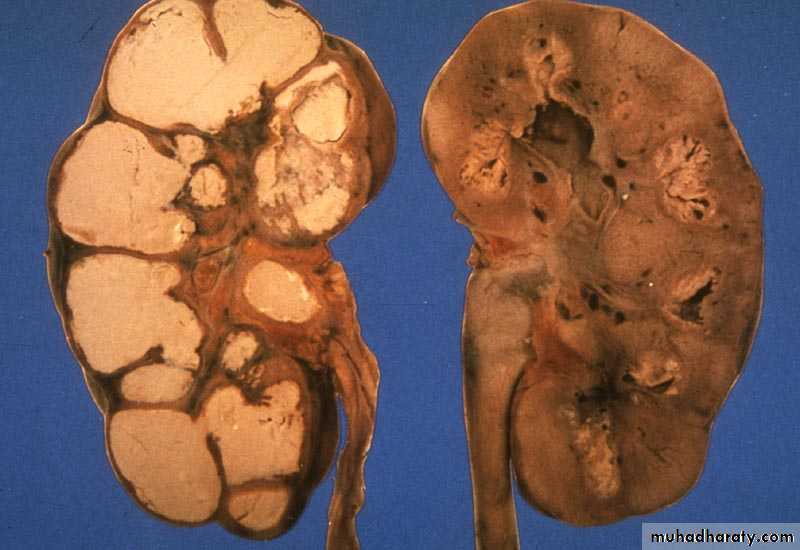

Renal Tuberculosis

Bacteria: Mycobacterium TB

Pathogenesis: Hematogenic

Start unilateral , late bilateral affection.

The 1st lesion starts usually in the pyramids

Chronic: Asymptomatic until late stage

TB granuloma, caseation, open to the calyces.

Renal destruction, calcification.

RENAL TB

KUB: Renal calcification